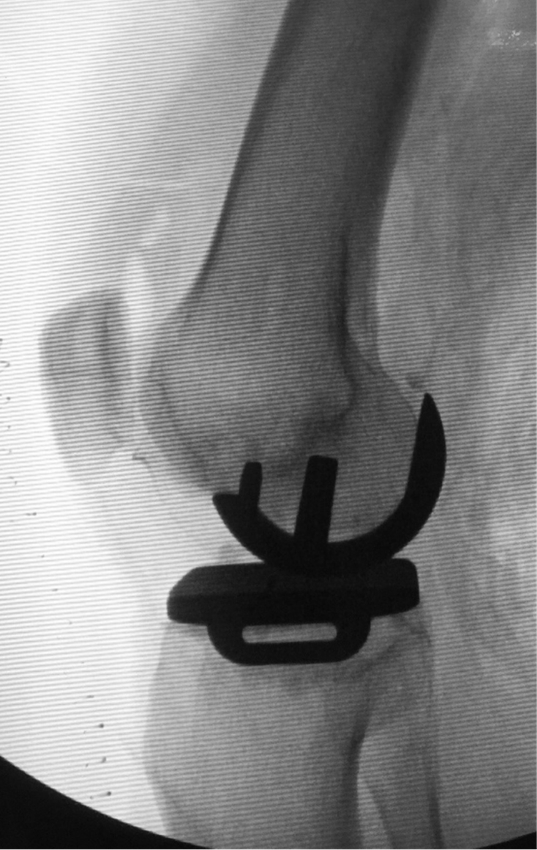

术中膝关节正位X线